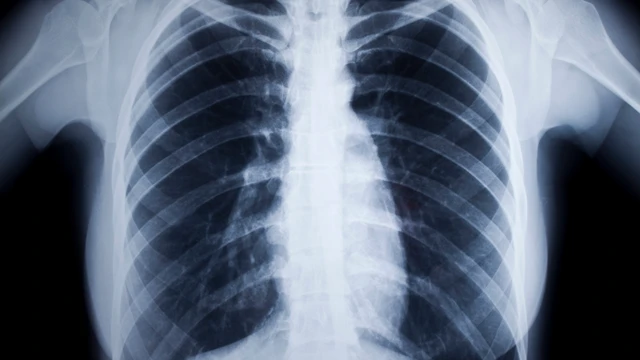

Sức khỏe răng miệng đóng vai trò quan trọng trong sự phát triển toàn diện của trẻ em, đặc biệt trong những năm đầu đời khi răng và xương hàm đang hoàn thiện. Trong quá trình thăm khám nha khoa, nhiều trẻ được bác sĩ chỉ định chụp X-quang răng để đánh giá chính xác tình trạng bên trong răng và xương hàm. Bài viết dưới đây, nhà thuốc Long Châu sẽ giúp ba mẹ hiểu rõ vai trò, mức độ an toàn và những lưu ý quan trọng khi chụp X-quang răng cho trẻ em.